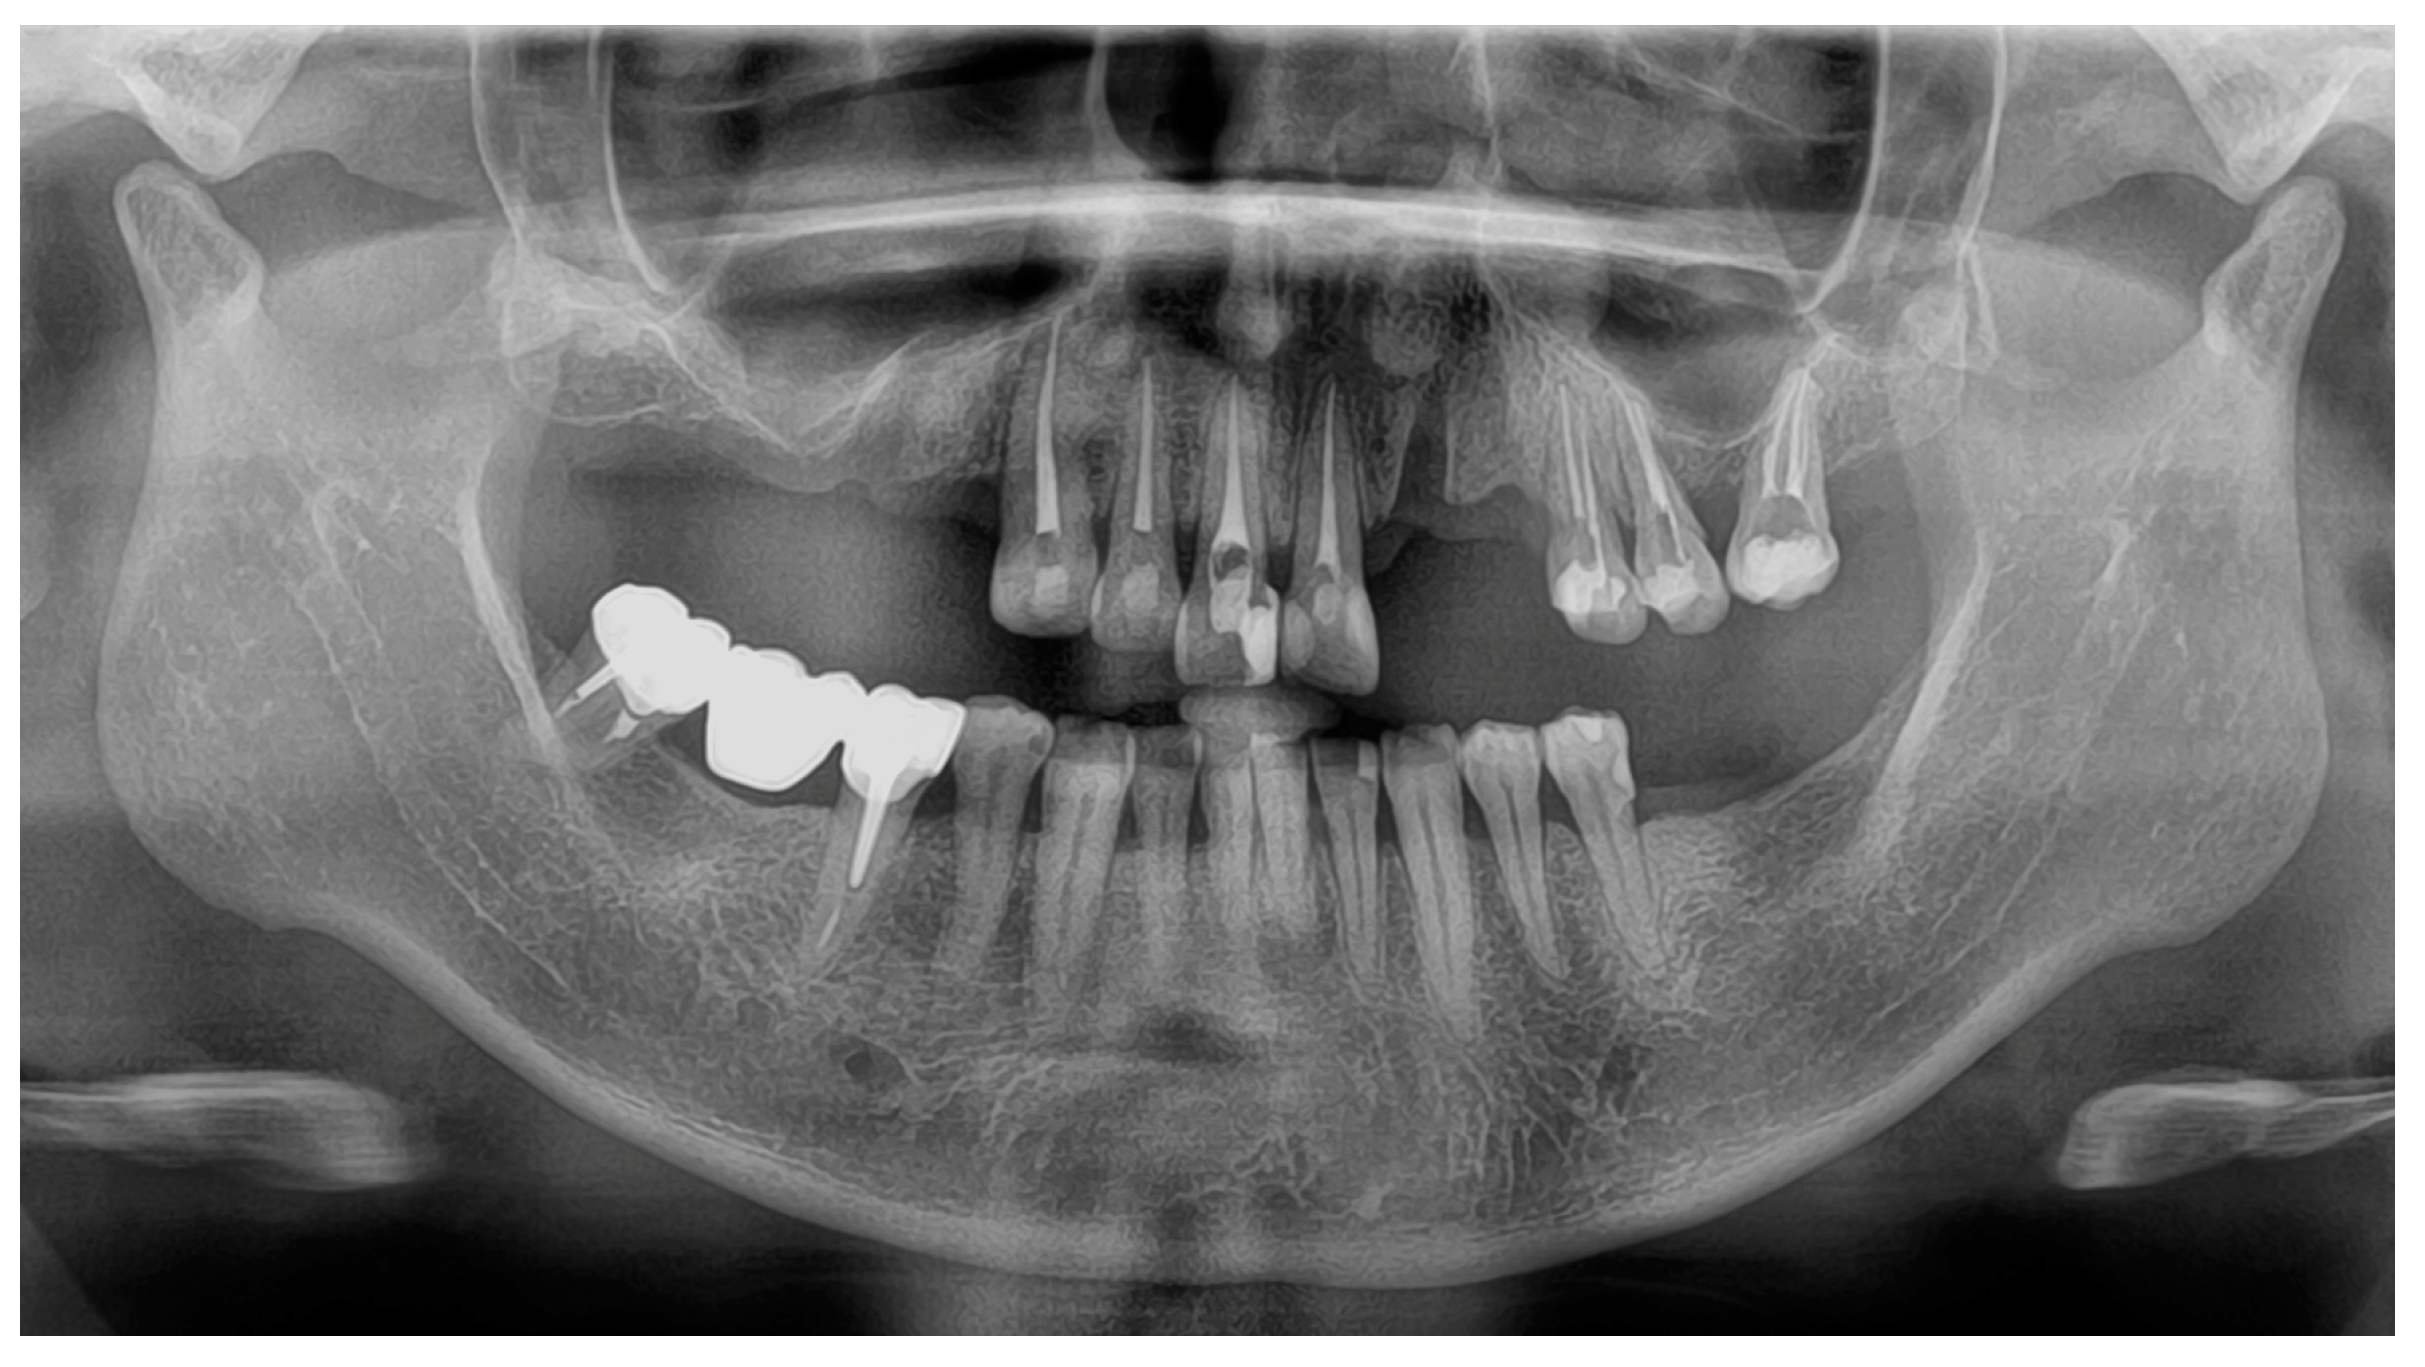

Digital impressions of the patient’s existing maxillary and mandibular arches and the MMR were obtained using the intraoral scanner (TRIOS 4; 3Shape A/S) (Figure 2A). The digital complete-arch casts were imported and aligned into the jaw motion system (MODJAW; MODJAW). The mandibular movements were registered following the manufacturer’s protocol (Figure 2B). Finally, the patient’s face was digitized with the facial scanner (Bellus3D Face Camera Pro; Bellus3D) and the AFT (AFT dental system) protocol (face and teeth aligners) (Figure 2C) [19].

Figure 2. Digital view of the initial situation: (A) 3D images (TRIOS 4; 3Shape A/S) of maxillary, mandibular, and MMR captured by IOSs; (B) functional mandibular movements recording with the jaw motion tracer (MODJAW; MODJAW); and (C) facial scans (Bellus3D Face Camera Pro; Bellus3D) with AFT aligners.